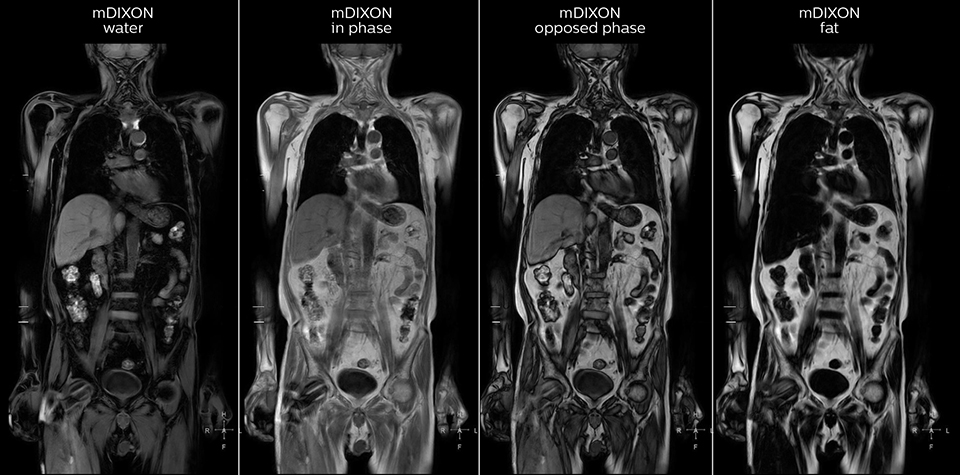

mDIXON FFE enriches the whole body exam without scan time penalty

Kawasaki Sawai Hospital’s whole body protocol also includes an mDIXON FFE sequence. Because mDIXON provides images for four contrast types – water only, fat only, in-phase and out-of-phase – from a single acquisition, it is useful in many ways.

“mDIXON FFE allows us to quickly get information we need to assess the presence of fat. That gives us more information when we need to diagnose bone lesions, and when we are asked to judge fat-containing lesions such as hepatocellular or renal carcinoma,” Dr. Nobusawa says.

“The mDIXON fat images can help us to differentiate fatty bone marrow from bone lesions. This is especially useful in elderly people, who tend to have fattier bone marrow. The water images provide a high signal-to-noise ratio in the intestinal canal, which is valuable for visualizing lesions in the colon,” he says.

“In-phase and out-phase sagittal T1-weighted FFE images help us to visualize and further characterize bone lesions such as metastasis and bone-marrow hyperplasia that have high signal on DWI. These images are also used throughout radiotherapy, to monitor changes in the fatty bone marrow.”